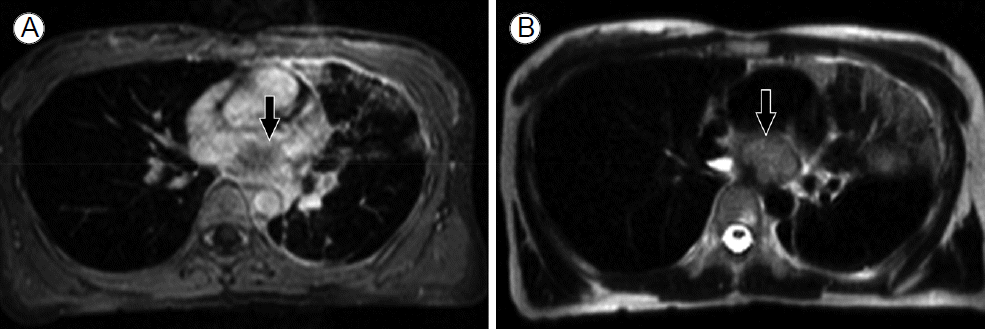

심장 자기공명영상(magnetic resonance imaging) 소견: 좌심방 종괴는 T2 weighted 영상에서는 고신호 강도(high signal intensity), T1 weighted 영상에서는 동신호 강도(Iso-signal intensity)로 나타났으며, 균일하지 않은 조영 증강을 보였다(Fig. 3).

Figure 3.

Contrast-enhanced magnetic resonance imaging of the heart in (A) T1-weighted and (B) T2-weighted views. A well-circumscribed, dumbbell-shaped lesion was observed, which showed high-signal intensity in the T2-weighted image and iso-signal intensity in the T1-weighted image (arrows).